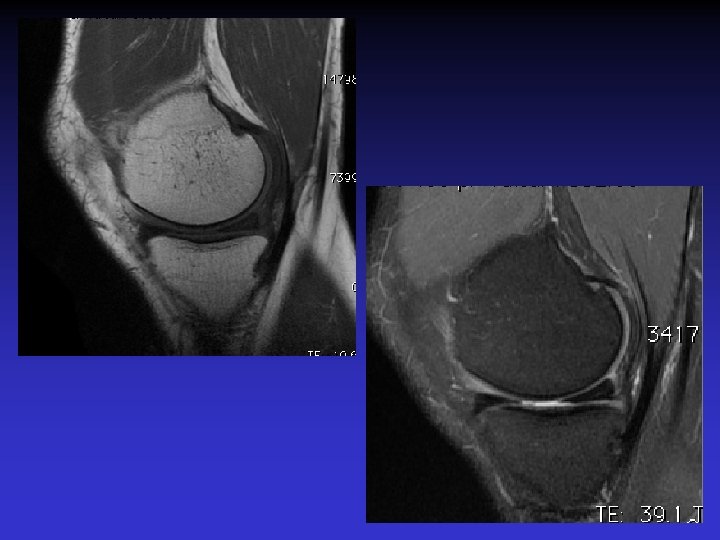

• Homme de 46 ans • Douleurs et sensation de blocage du genou • Pas de traumatisme récent mais « entorse ancienne » • Recherche de lésion méniscale

• • • Pas d’épanchement Pas de lésion méniscale Pas de lésion cartilagineuse Pas de lésion osseuse Anomalies du LCA • Épaissi • Hyper signal T 1 et T 2 • Orientation des fibres conservée • Kyste

ASPECT IRM • • Hyposignal TI Hypersignal T 2 Pas de prise du contraste après Gado IV Continuité conservée du LCA+++ avec dilacération des fibres • Aspect en « tige de céleri »